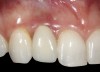

The crown and screw-retained custom abutment were removed, and a surgical cover screw was placed into the implant, thereby allowing spontaneous gingival augmentation in situ (Figure 33 and Figure 34). Note that the lingual aspect of the implant site was significantly more coronal than the labial aspect, which was positive because the defect would be limited to a facial–lingual defect. A fixed RBR bridge was cemented on the adjacent teeth and used as a tooth-supported transitional provisional restoration (Figure 35). A few weeks were allotted to let the soft tissue heal and migrate around the cover screw (Figure 36) to see if there would be complete coverage, thereby allowing a soft-tissue augmentation procedure to be performed with primary flap closure as in clinical scenario No. 2. The major obstacle in achieving a positive tissue response was that the implant depth was also deficient because the implant–abutment connection was at the level of the free gingival margin. It was decided that the best treatment option would be to remove the implant. A high-powered reverse-torque device (Fixture Remover Kit, NeoBiotech, www.neobiotechus.com) was used to remove the implant atraumatically (Figure 38 through Figure 41). The implant socket was allowed to heal for several months not unlike an extracted tooth (Figure 42). A new implant was placed in a better position from both a restorative and esthetic perspective (Figure 43), and after a few months of healing, a new crown was made (Figure 44). A satisfactory functional and esthetic result was achieved (Figure 45 and Figure 46) without employing pink porcelain.

Fig 45. The definitive crown tooth No. 26 seated in place and provisionally cemented. The recession defect was eliminated with the removal and replacement of a new implant in the proper position.

Fig 46. The post-treatment radiograph showing a healthy stable implant and restoration.